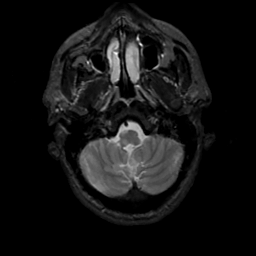

MR Study #6, March 17, 1991 -- Slice #7